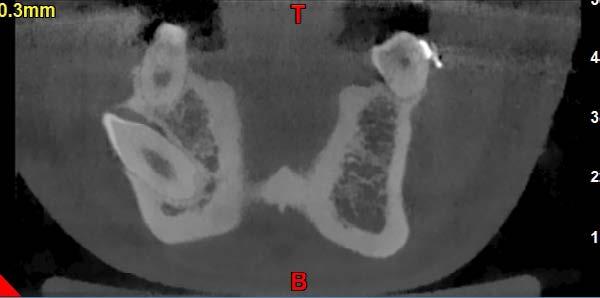

Figura 7 Cone-beam de control de la zona más distal del primer cuadrante donde se planifica un implante extracorto

Para elaborar la planificación de los implantes a colocar se realiza en primera instancia un TAC, observándose en el mismo que existe un déficit de altura en todo el maxilar superior.

Todos los dientes conservados reciben un mantenimiento periodontal riguroso (Figura 4-6). Transcurridos 2 meses, comenzamos con la rehabilitación del maxilar superior mediante implantes. Durante este tiempo se lleva a cabo la inserción y rehabilitación provisional mediante prótesis de carga inmediata de la mandíbula. Para elaborar la planificación de los implantes a colocar se realiza en primera instancia un TAC, observándose en el mismo que existe un déficit de altura en todo el maxilar superior, siendo más acusada la atrofia en altura en la zona de los molares. En el primer cuadrante, tenemos una altura ósea de 5.5 mm por lo que podemos planificar la colocación de un implante extracorto (5.5 mm de longitud y 5.5 mm de diámetro) con elevación de seno transcrestal (Figura 7). En el segundo cuadrante, existe una atrofia ósea en altura mucho mayor con menos de 1 mm de altura, existiendo áreas donde se produce una ruptura

en la continuidad de este reborde óseo, por lo que la mejor alternativa terapéutica es la realización de una elevación de seno mediante abordaje lateral (convencional) (Figura 8).